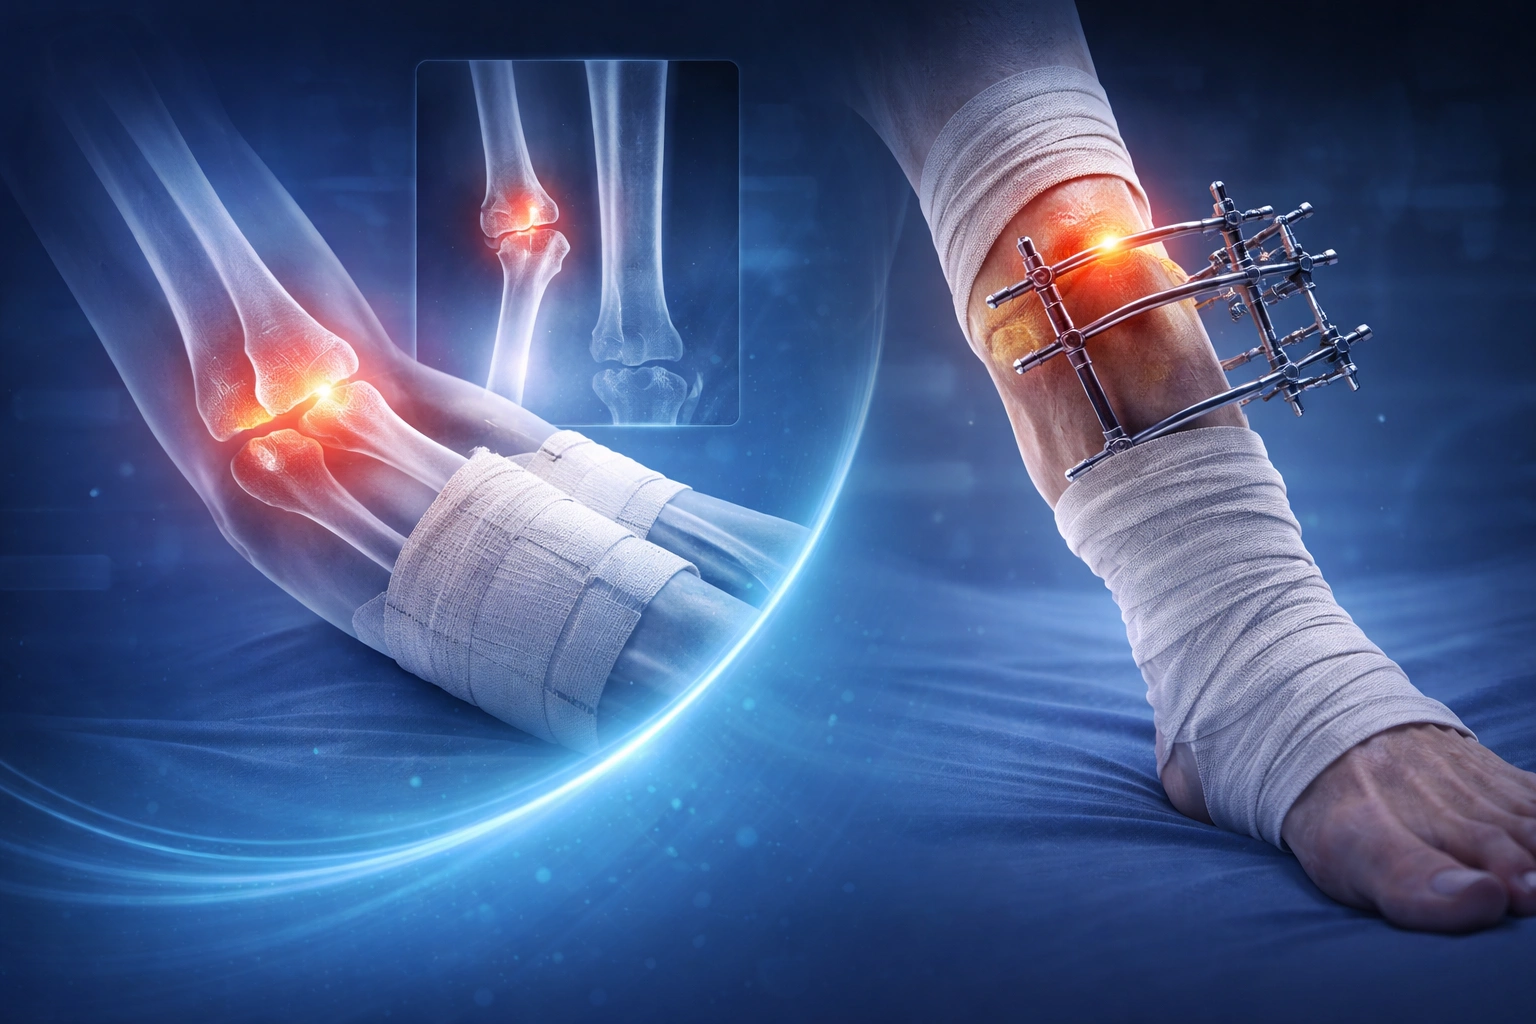

Procedimientos especializados para restaurar la función y movilidad articular.

Tratamiento integral para recuperación ósea y funcional.

Tratamientos biológicos enfocados en la regeneracion de tejidos.